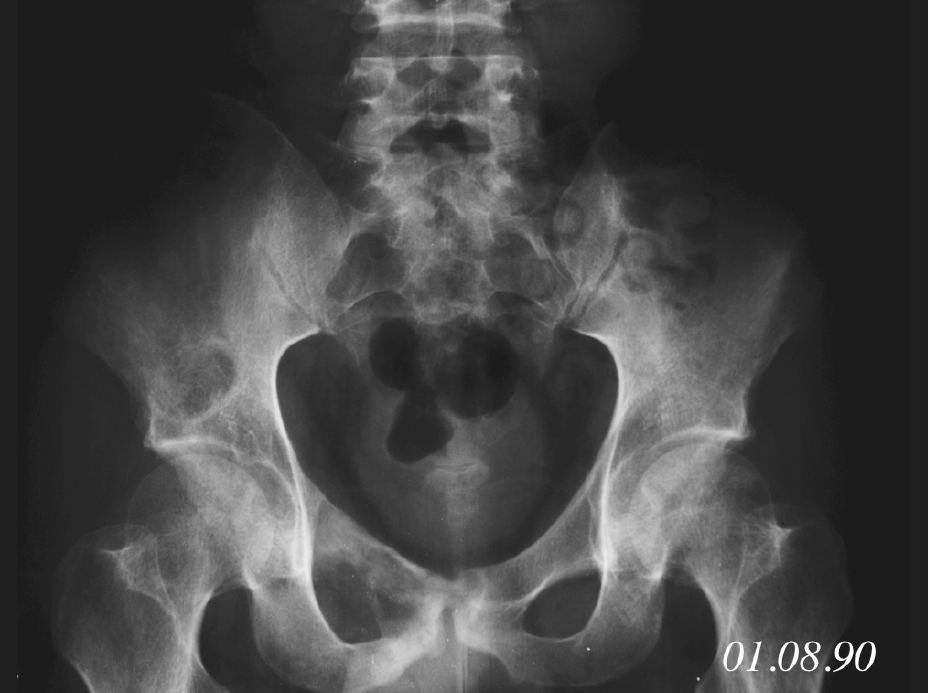

Figure1